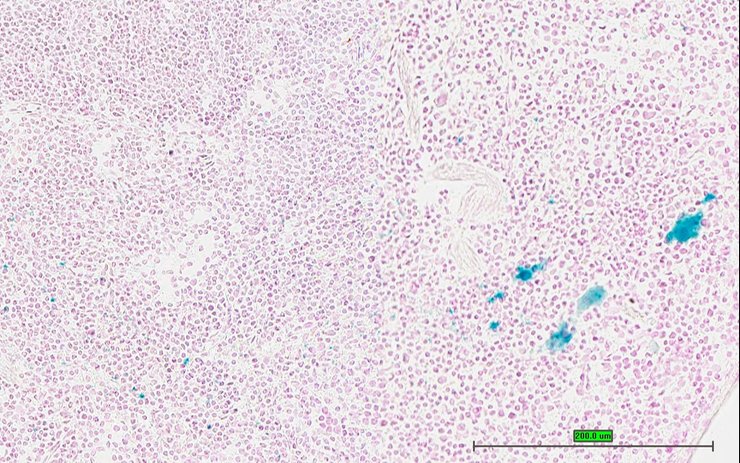

TS28: spleen Present UC Davis_1875950

Specimen UC Davis_1875951: postnatal adult; Ppbptm1.1(KOMP)Vlcg/Ppbp+ (more )

Structure Level Pattern Image Note

TS28: spleen Present UC Davis_1875951

TS28: spleen Present UC Davis_1875968

Specimen UC Davis_1875969: postnatal adult; Ppbptm1.1(KOMP)Vlcg/Ppbp+ (more )

TS28: spleen Present UC Davis_1875969